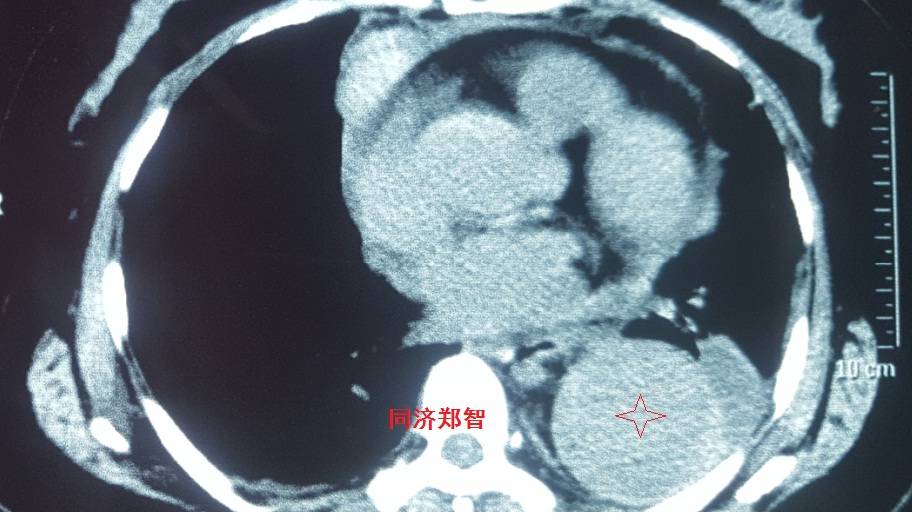

病例二

胸部平扫CT提示升主动脉增宽(红色星形标记),CTA证实A型主动脉夹层伴升主动脉夹层动脉瘤形成。